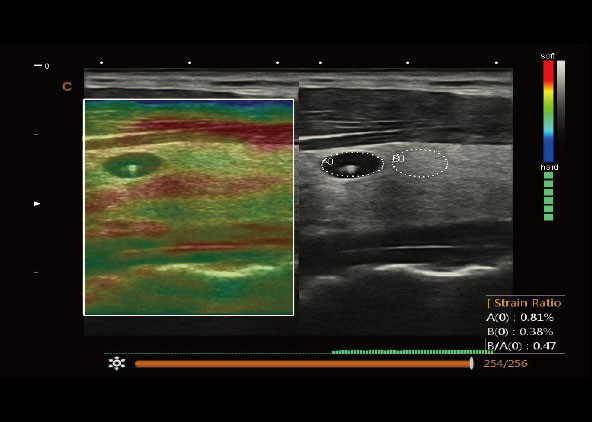

Elastography

Evaluate the tissue stiffness, strain ratio measurement, fine technology for breast lesion, thyroid tumor and liver scans.